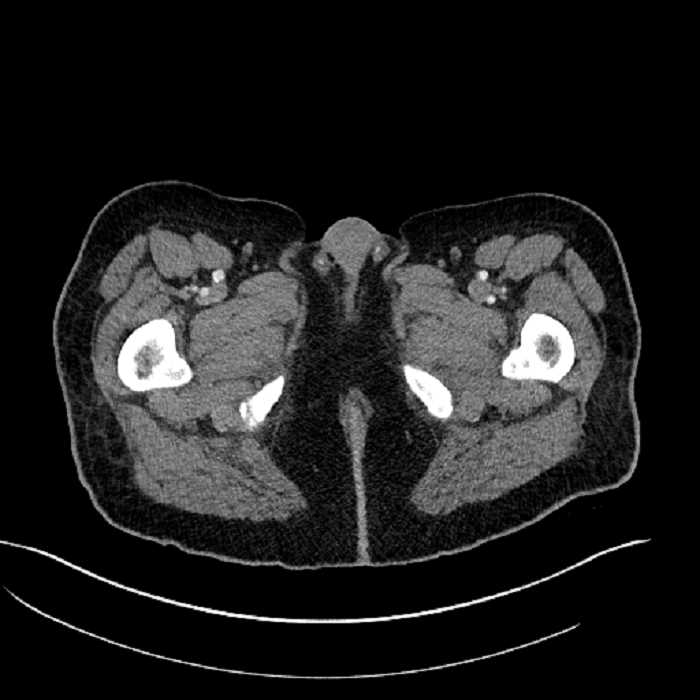

• High grade stenosis of the left common iliac artery, with the left internal and external iliac arteries remaining patent

High grade stenosis of the left common iliac artery. The left external and internal iliac arteries are patent.

Hepatic abscess showing the double target sign with low density internally surrounded by a thin inner enhancing rim (red arrow) and ill-defined outer low density rim (yellow arrow). Blue arrow indicates an internal septation. Red arrows: additional smaller subcapsular abscesses. Red arrow: focal contained perforation associated with diverticulitis.